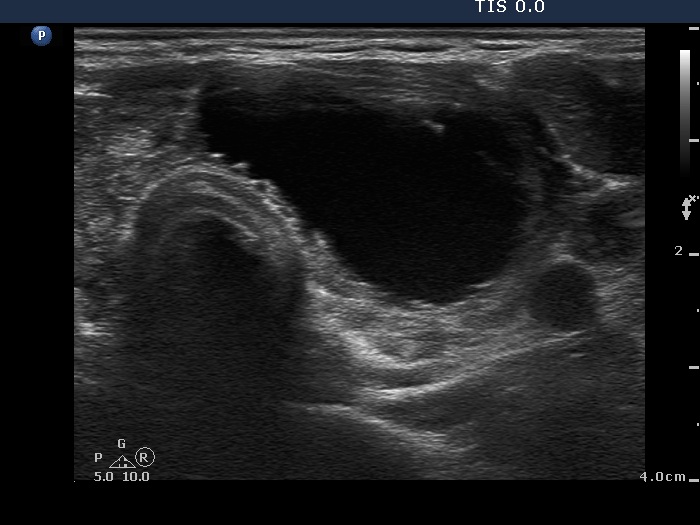

Second examination 2 month later (2nd row of images)

Clinical presentation: the cyst has recurred 2 weeks after aspiration.

Ultrasonography was identical to the previous examination.

Ethanol sclerotherapy was advised. Three sessions of ethanol injection were given and a total amount of 8 mL alcohol was administered. The first session is presented in 2nd row of images.